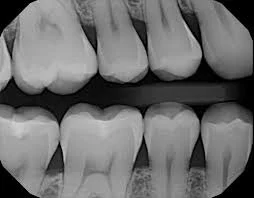

When looking in the mouth dental professionals look for multiple things, such as, tissue health, bone levels, oral cancer, and cavities. Although dental professionals can see most things in the mouth and on the teeth, unfortunately we cannot see everything. With teeth being so close together it is impossible for any dental professional to be able to properly diagnose cavities. The earlier we can diagnose a cavity, the simpler the solution. In the picture below you can see just how tight the teeth are together, making it difficult to see in between the teeth. When we take a bitewing or cavity detecting x-ray, we have a much better look in between the teeth. These x-rays are also beneficial in showing bone levels in the mouth, which contributes to a healthy mouth.

An x-ray of teeth is shown.

The reason we take these x-rays is to help detect disease in the mouth, and cavities. Cavities are full of bacteria, and as you eat and drink all day you spread this bacteria to the rest of your body, which can lead to many other health concerns. Another disease we find is in the form of bone loss. Again our x-rays show us the bone levels, and help us to detect if something needs to be addressed.